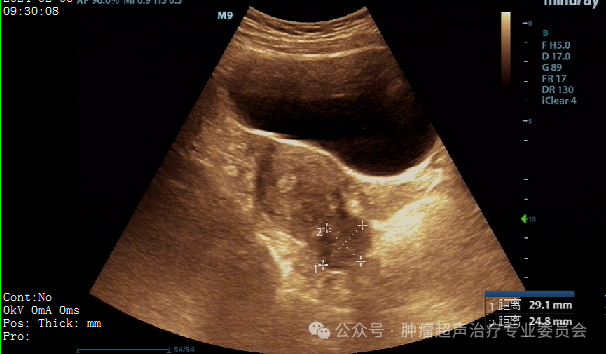

治疗前妇科彩超检查

子宫前壁见一个大小约44×27mm的低回声团;

后壁见一个大小约49×33mm的低回声团,6型。

子宫后壁肌瘤缩小至29*25mm,子宫前壁肌瘤

缩小至26*20mm。较治疗前缩小达40%。